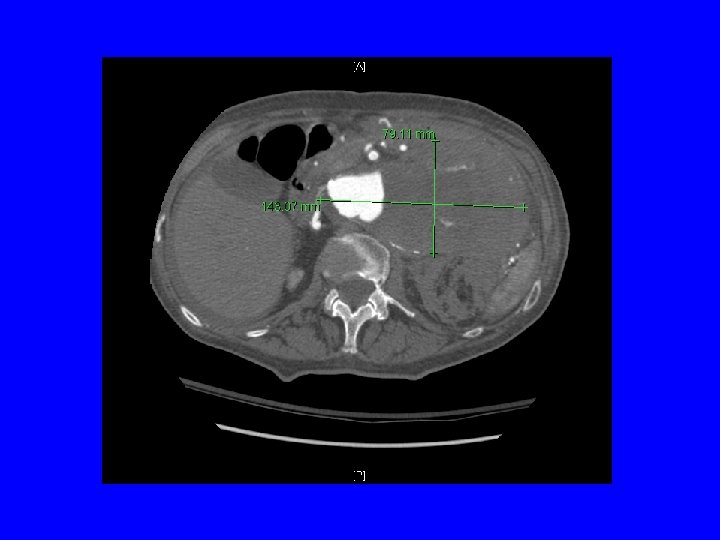

14 x 8 cm abdominal aortic aneurysm arising from the supraceliac aorta and extending to just above the take off of the left renal artery is visualized with extensive thrombus but also extensive flow

See presence of retroperitoneal blood. Here there is not a large retroperitoneal hematoma, but stranding of blood into surrounding tissues